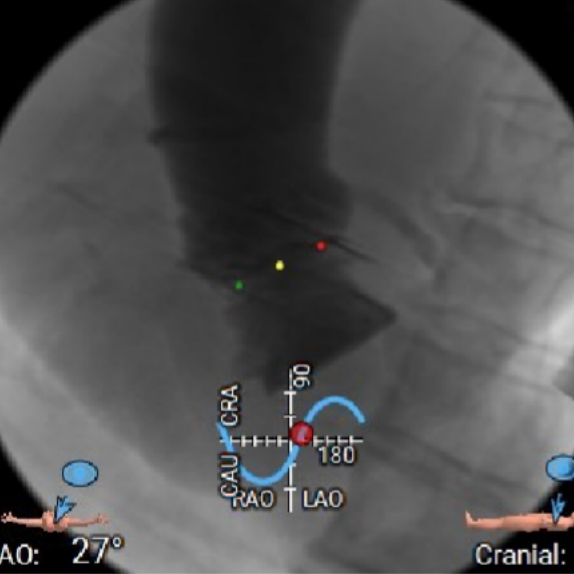

术中造影角度:右窦中心位 LAO 27°,CRA 9°。